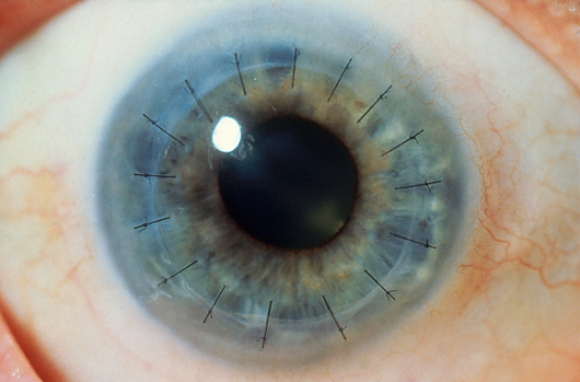

כ-12.7 מיליון איש עיוורים בגלל פגיעה בקרניות שלהם. קרנית מושתלת מחוברת למקום על ידי תפרים | צילום: RALPH C. EAGLE, JR. / SCIENCE PHOTO LIBRARY

החוקרים לא הסתפקו בכך, ופיתחו גם שיטת ניתוח חדשה. שיטות הניתוח שהיו מקובלות עד היום פגעו בעצבים ובתאי הקרנית הקיימת של המטופל. השיטה החדשה שפיתחו החוקרים דורשת חתך יחיד בקרנית הקיימת, שבעזרתו משתילים את הקרנית המהונדסת בלי צורך בתפרים ובלי לפגוע בעצבים שבקרנית. החוקרים בדקו את השיטה על חזירים ווידאו שהיא בטוחה בטרם השתמשו בה להשתלת קרנית בבני אדם.